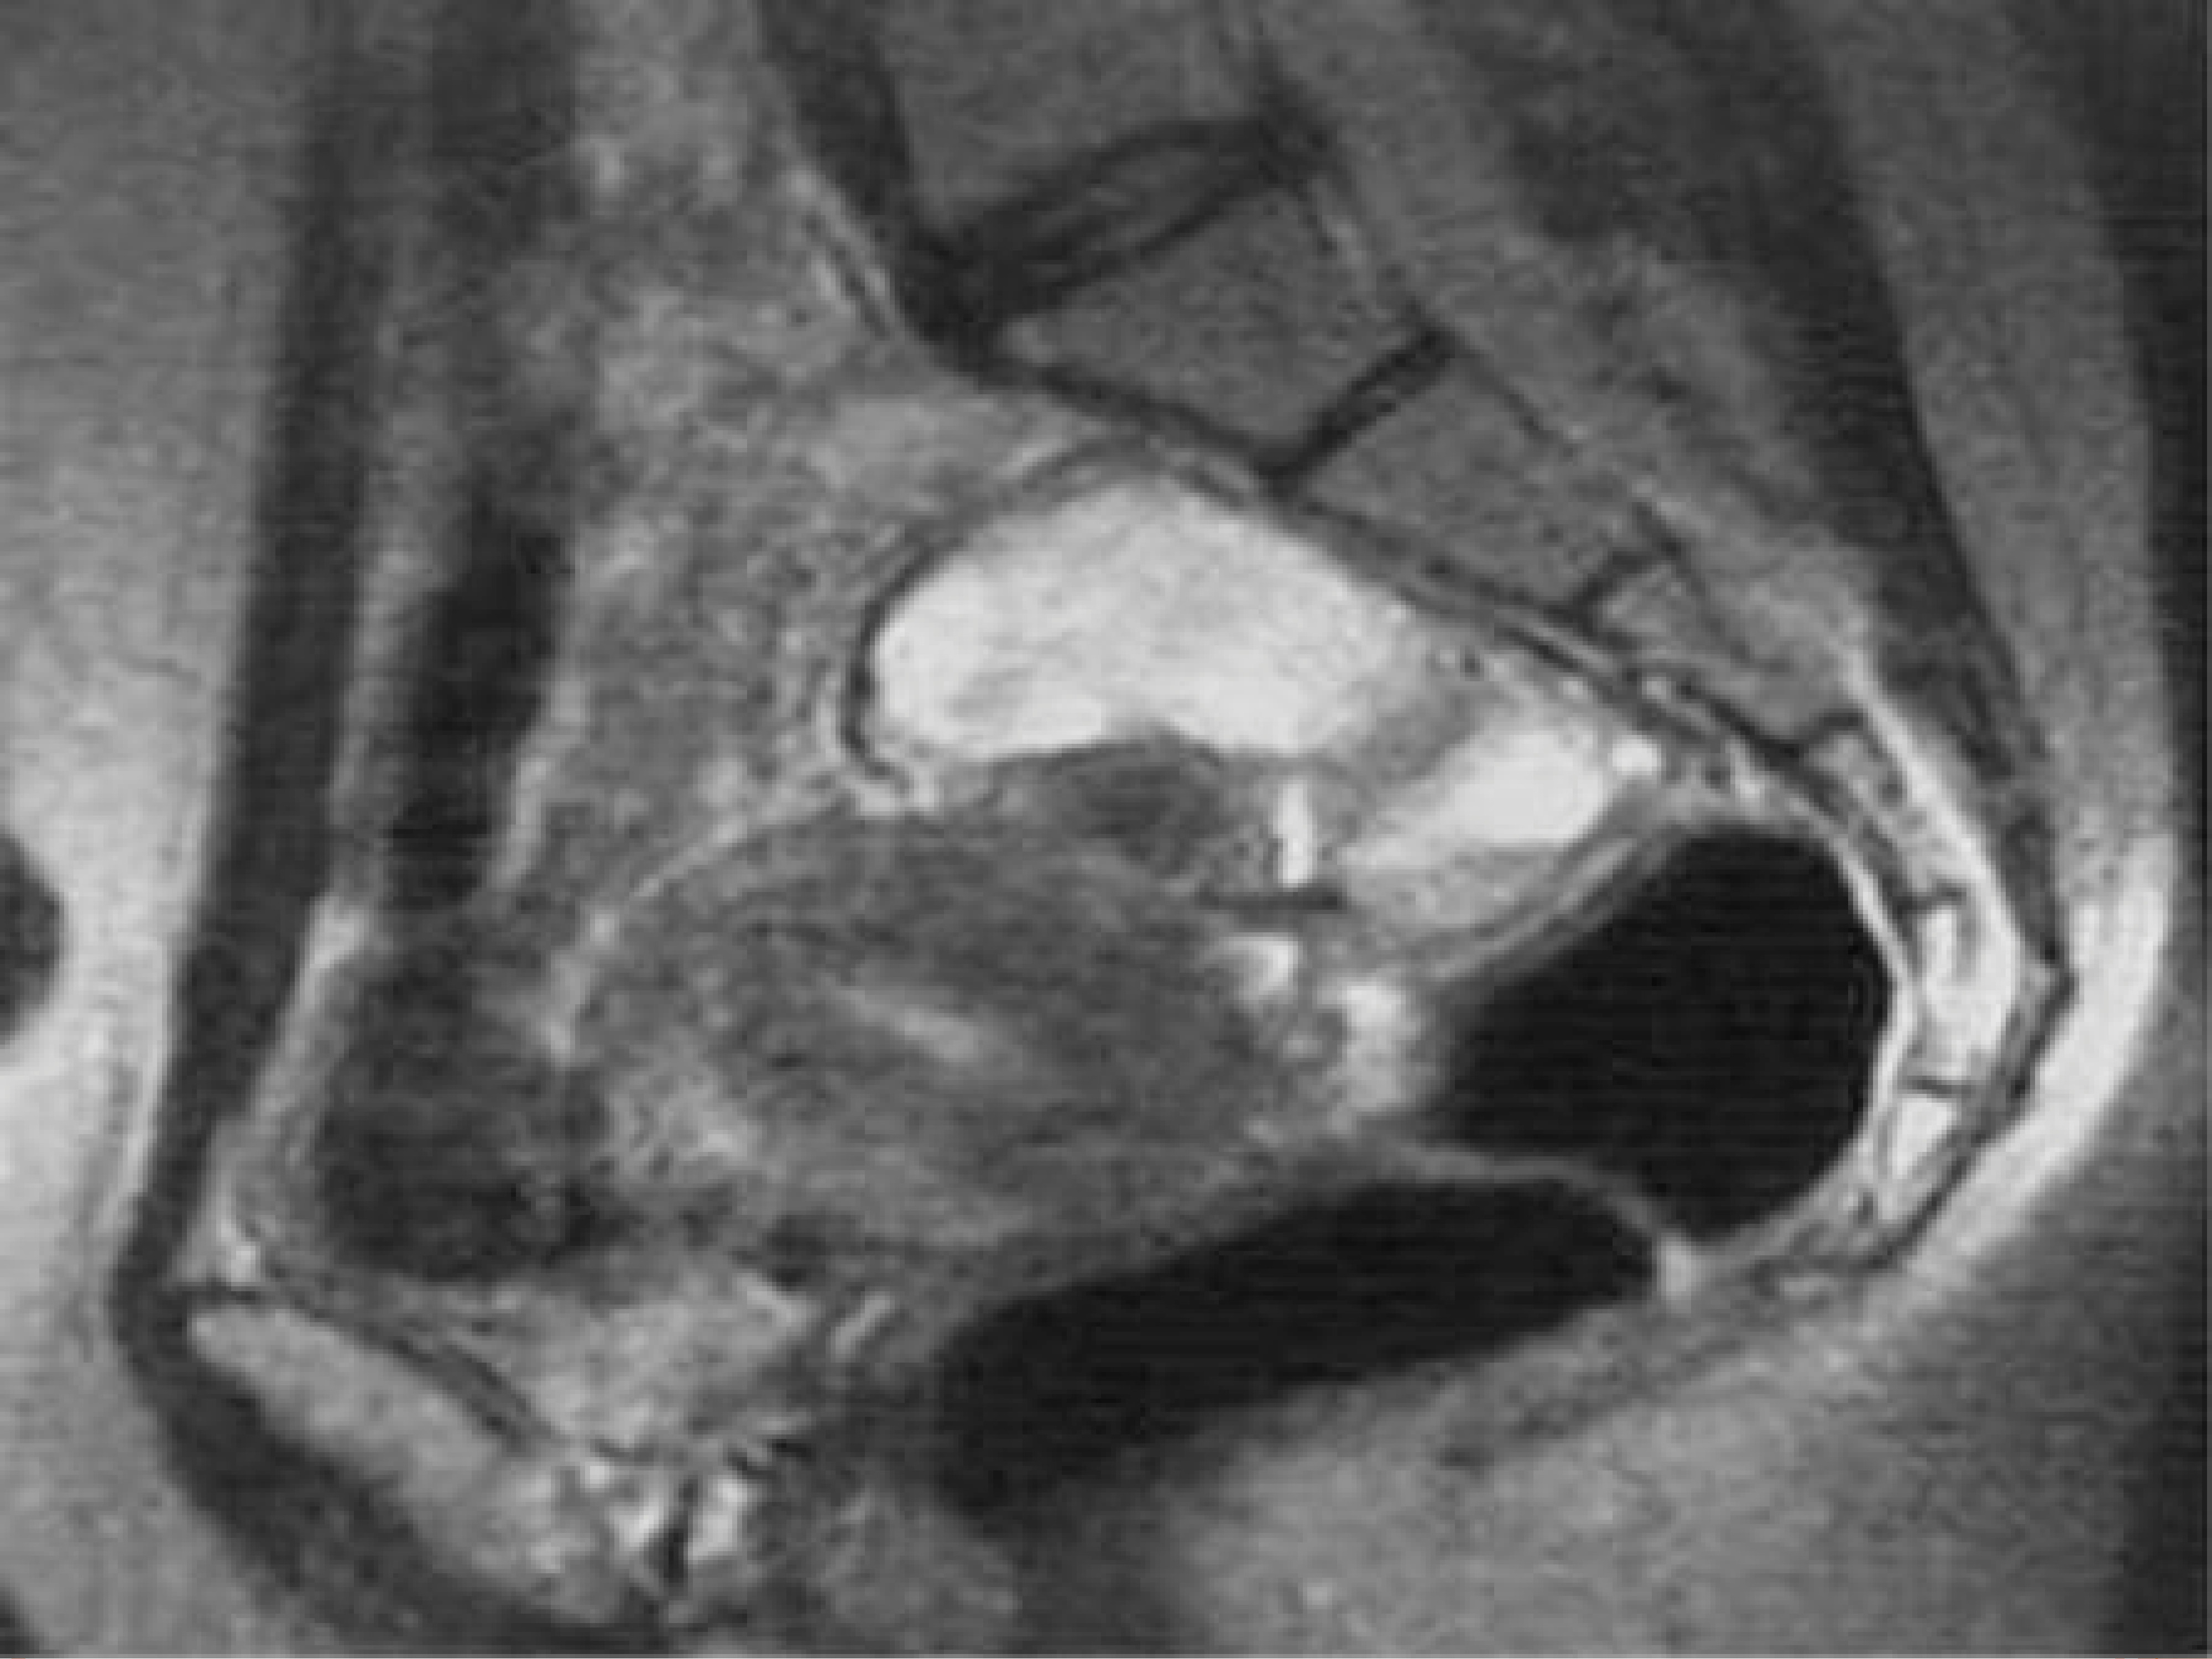

Гидросальпинкс мрт

Гидросальпинкс мрт 111 фотографий